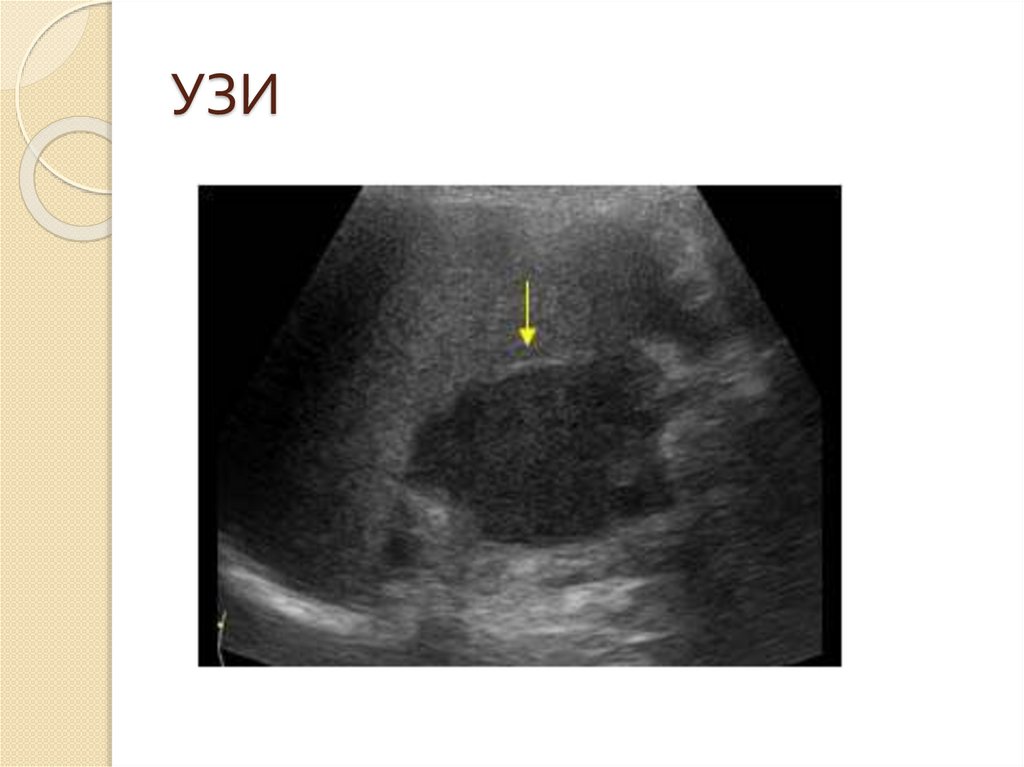

УЗИ

28. УЗИ